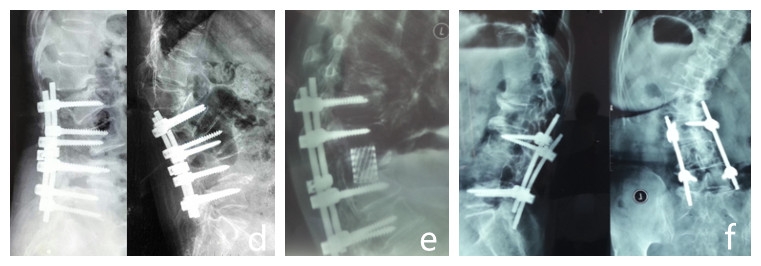

图3 PJK的分类

三、PJK的分类( Yagi,2012)(图3)

该分类提供了临床医生描述类型和严重程度的方法,但对治疗无指导作用。

类型

1.韧带的损伤和破坏

2.骨性结构的破坏

3.内固定的失败

PJA角度分级

A:PJA10-14°

B: PJA15-19°

C: PJA>20°

滑脱

N:上终椎UIV上方无滑脱

S:有滑脱